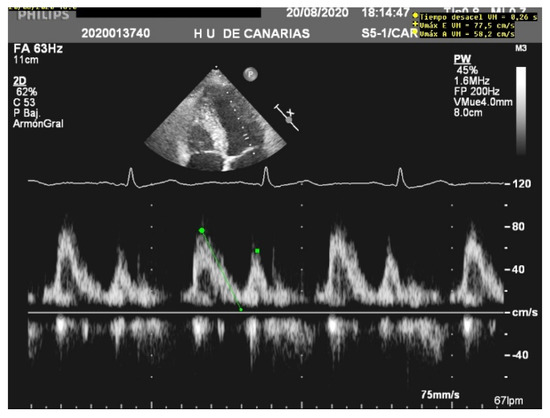

Unlike MV weaning assessment, evaluation of systolic function is the key factor in the decision to wean from ECMO. Weaning can be attempted when the ejection fraction of the left ventricle is higher than 35% and/or the left-ventricular outflow tract velocity time integral (VTI) is higher than 15 cm/s, with a minimal ECMO flow under 1.5 L/min or less than 1500 rpm [9]. Previous studies have also proposed lower values of both ejection fraction (around 20–25%) and VTI (10 cm/s) for a successful weaning [32,33] (Figure 3 and Figure 4).

Figure 3.

Normal left-ventricular outflow tract velocity integral (VTI).